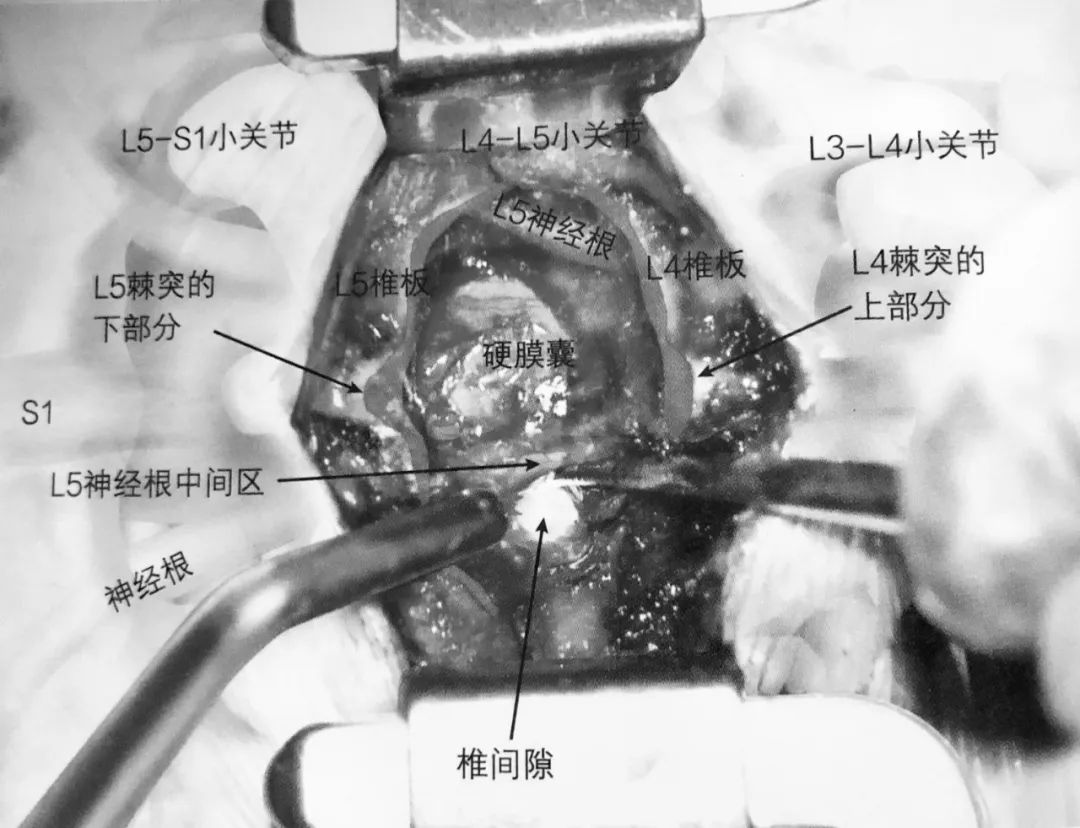

1. 术前准备要点:

2. 皮肤切口:后正中切口

3. 切开前确认筋膜

4. 逐层确认筋膜并在棘突正中上方打开,应用 Cobb 骨膜剥离器进行骨膜下剥离

5. 暴露椎板直至关节囊内侧部分

6. L4 棘突的下部分及 L5 棘突的上部分,连同棘上韧带、棘间韧带一起去除

7. 应用枪钳去除黄韧带

8. 通过潜行咬除下位椎体的上关节突来对侧隐窝进行减压

9. 将神经根轻柔牵向内侧,暴露椎间盘,清楚暴露硬膜囊及神经根

10. 应用尖刀在突出椎间盘上切开纤维环

11. 髓核钳咬除椎间盘组织

12. 潜在风险:如果手术做错了间隙,通常是在应手术的上一个节段。如果没有发现预期的病变,在切开纤维环之前需要透视或摄 X 片证实